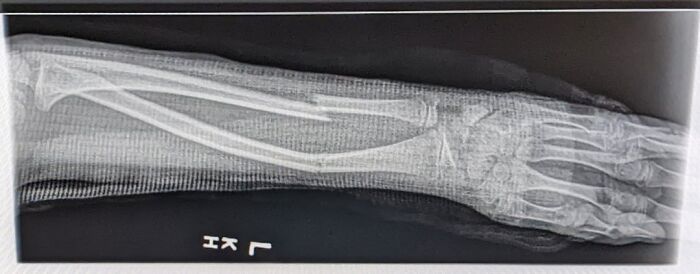

Una máquina de pinball de anatomía